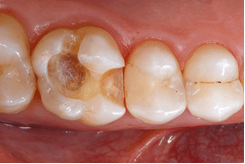

Afb. 1: Uitgangssituatie: Insufficiënte composietvulling in element 16 (foto via intra-orale spiegel).

Afb. 2: Na het verwijderen van de cariës werd de caviteit gepolijst.